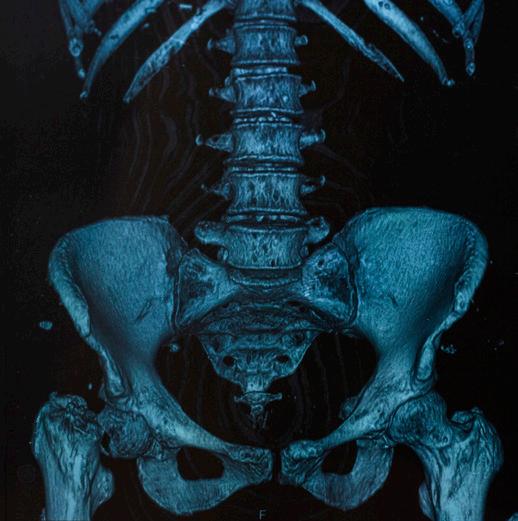

Computed tomography (CT), also called computed axial tomography (CAT), is a radiological study that uses X-ray technology to create a crosssectional, three-dimensional image of the inside of the body. It is a more precise study than X-ray and can provide clear, detailed images of bone.

¡ CT allows for the detection of small bone lesions that are not detectable by plain X-rays. In 20%–25% of patients with negative X-ray studies, whole-body CT will detect destructive bone lesions.

¡ CT can detect soft tissue masses that are not visible on X-ray.

¡ CT provides a more comprehensive assessment of fracture risk and the stability of collapsed vertebrae than X-ray.

To detect and document early bone disease, the IMWG recommends the use of whole-body low-dose CT (WBLDCT) as the preferred baseline imaging study for newly diagnosed myeloma patients. It has the following advantages:

¡ WBLDCT is faster and more convenient than WBXR.

¡ WBLDCT uses two to three times less radiation than conventional CT.

¡ WBLDCT does not require the use of contrast agents.

In 2017, the IMWG published a study, concluding that whole-body CT, either alone or as part of a PET-CT protocol, should be considered the current standard for the detection of osteolytic lesions in myeloma.

In 2018, the IMWG published its recommendations for acquisition, interpretation, and reporting of WBLDCT in patients with myeloma and other plasma cell disorders, thus establishing international protocol standards for this imaging study that can be followed by radiologists everywhere.

In 2019, the IMWG published guidelines on optimal use of imaging methods at different disease stages.

Despite its advantages, limitations of CT include:

¡ Like MRI, CT cannot be used for treatment monitoring because bone lesions in myeloma regress slowly or not at all, even in patients in complete remission.

¡ CT is not as sensitive as MRI in detecting lesions outside the bone marrow (extramedullary disease) or in the vertebrae and pelvis.

¡ CT is an expensive study.

¡ Even in low-dose format, CT uses an increased level of radiation as compared to X-ray or to MRI, which doesn’t use radiation at all.